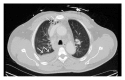

A 50-year-old male with a history of hemodialysis dependent chronic kidney disease presented to our emergency department with acute midsternal crushing chest pain. Patient was diagnosed with acute anterolateral wall Myocardial Infraction due to the presence of corresponding ST segment elevations in EKG and underwent emergent cardiac catheterization which revealed normal patent coronaries without any disease. He continued to have chest pain for which CT of the chest was done which revealed pneumomediastinum with mediastinal hematoma, due to the recent attempted thrombectomy for thrombus in his right brachiocephalic vein.